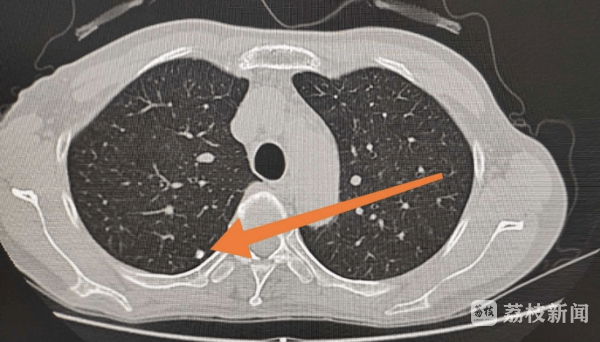

南京市中西医结合医院放射科主任唐晨虎主任医师介绍说,筛查是发现早期肺癌最有效的手段,但是筛查的方法很重要。一般的普通体检中,最常见的肺部检查是胸部X线透视,这种筛查方法对发现肺部结节有较大的局限性。因为分辨率较低,如有病变部位也容易受到纵隔、心脏、肋骨、胸骨等组织结构的重叠,无法辨识肺部的小结节,容易出现漏诊的情况。低剂量螺旋CT对于肺癌的检出率更高,几毫米的肺部结节都可以发现。而且其产生的放射剂量比常规CT更低,对人体影响很小,更适合用于肺癌的常规筛查。

南京市中西医结合医院肺病科(呼吸内科)主任李芳主任医师建议,对于肺癌的高危人群,可以在每年的体检中增加此类筛查,需要强调的是,低剂量螺旋CT只能查出可疑病变,如检查结果出现异常,需要进一步明确诊断,对于高度怀疑转移性病灶应积极寻找原发病灶,条件允许的情况下可采用支气管镜下活检或者肺穿刺检查,进一步明确病理学依据,病理活检才是诊断肺癌的“金标准”。

中医认为此病多因“郁”而起

2022版中华医学会肺癌临床指南(下称“指南”)中推荐,对经筛查发现的肺部结节应根据结节的位置、尺寸和密度特征进行分类管理。对于位于气道的病变或影像学高度疑似肺癌的情况,应采取临床干预。对于<5mm的(部分)实性结节或<8mm的非实性结节,推荐下年度低剂量螺旋CT检查;对于≥5mm的(部分)实性结节或≥8mm的非实性结节,推荐3个月后CT检查;对于无法排除非肿瘤的结节,推荐先进行抗炎治疗或随访,一个月后复查CT。